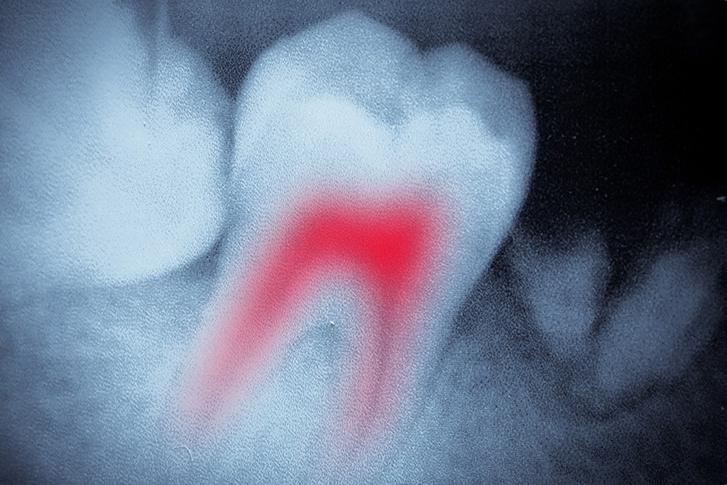

Root canal therapy is a treatment option that removes decay or infection from inside an affected tooth. The most common reasons for a tooth becoming compromised and requiring root canal treatment is due to untreated cracks or fractures, deep cavities, or injuries to the tooth. In order to save the tooth from extraction, the pulp (the living tissue inside the tooth), bacteria, nerves and any decay are removed. The area is cleaned and disinfected, and the resulting space is filled with special medicated dental materials which restores the tooth to its full function. An injured tooth that is left untreated can lead to a dental abscess, extreme pain, or possible tooth loss.